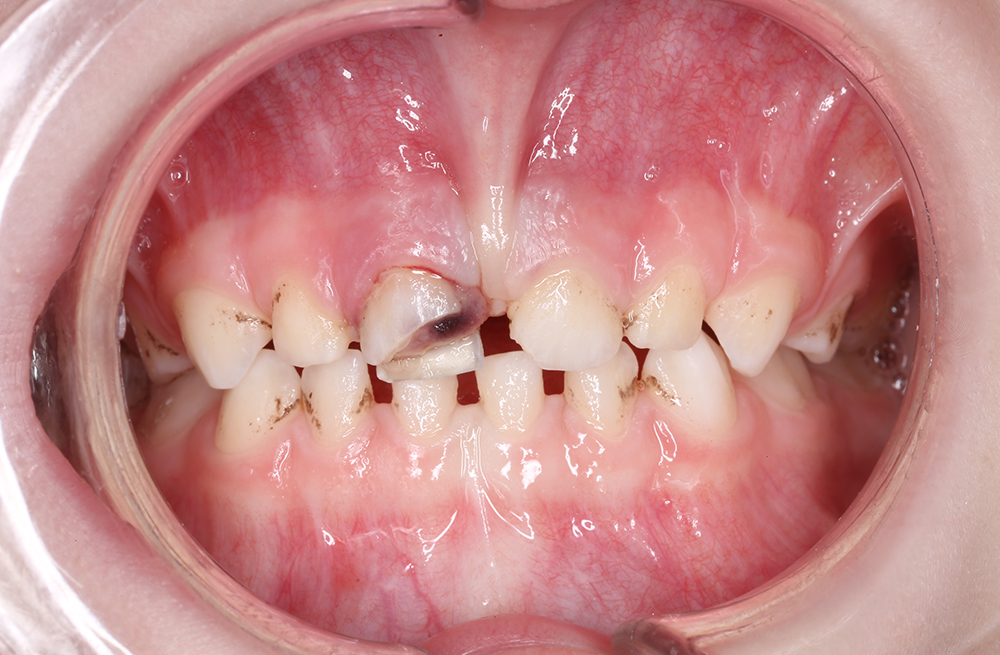

Комплексное восстановление молочных зубов при кариесе и пульпите у ребёнка 4х лет

Лечение и восстановление зубов во сне за один визит ребенку 6 лет

Лечение хронического пульпита с установкой коронки на зуб ребенку

Как мы вылечили пульпит и сохранили молочный зуб у ребёнка 5 лет

Как мы сохранили молочный зуб коронкой после лечения сложного пульпита у ребёнка под ЗАКС

Детское лечение пульпита без боли с сохранением зуба

Восстановление молочного зуба у ребёнка после глубинного кариеса дентина

Восстановление молочного зуба с помощью коронки при пульпите